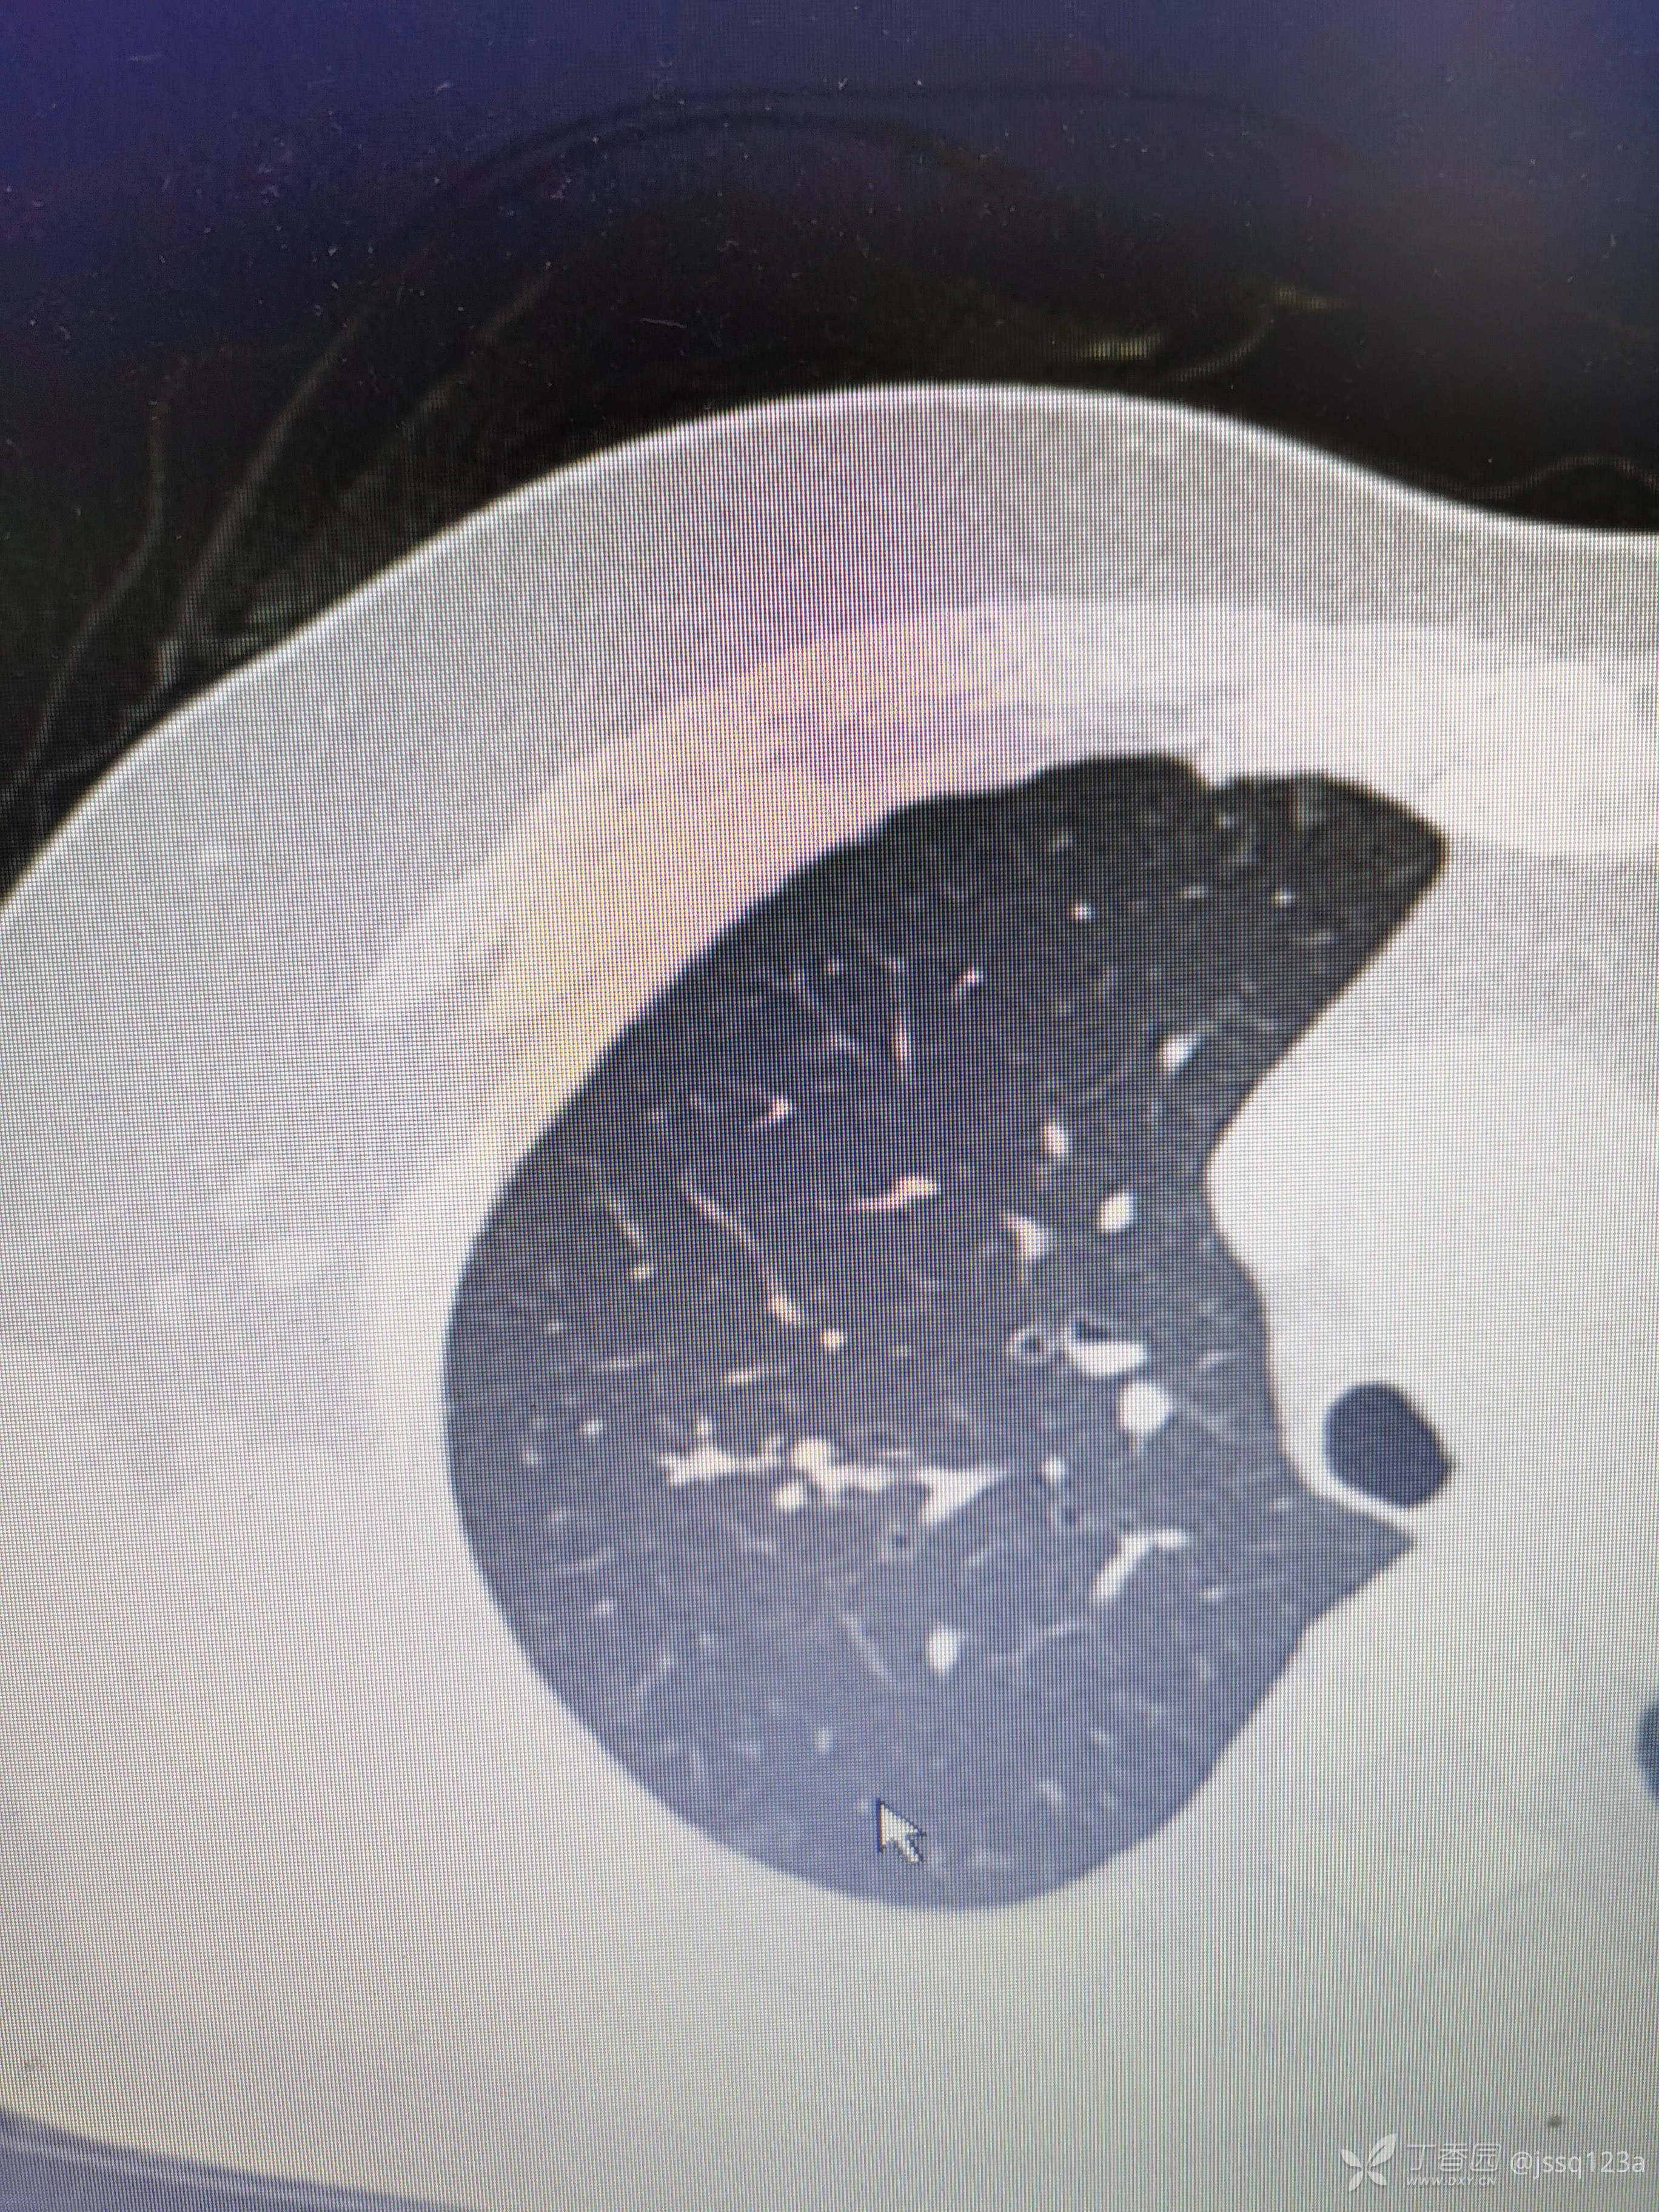

入院前胸部ct